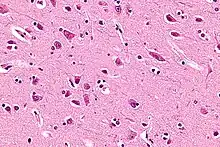

Based on cerebral cytoarchitectonics it has been divided into the Brodmann areas 23, 24, 26, 29, 30, 31, 32 and 33. The areas 26, 29 and 30 are usually referred to as the retrosplenial areas.

A study of the volume of the gray and white matter in the anterior cingulate gyrus in people with schizophrenia and their healthy first and second degree relatives revealed no significant difference in the volume of the white matter in the people with schizophrenia and their healthy relatives. Nonetheless a significant difference in the volume of gray matter was detected, people with schizophrenia had smaller volume of gray matter than their second degree relatives, but not relative to their first degree relatives. Both the person with schizophrenia and their first degree healthy relatives have smaller gray matter volume than the second degree healthy relatives. It appears that genes are responsible for the decreased volume of gray matter in people with schizophrenia.[18]